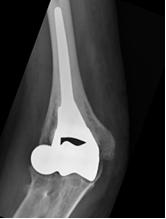

1) Protesi totale di gomito: riproduce la superficie articolare del gomito mediante due componenti, una omerale e l’altra ulnare (Fig. 3). L’accoppiamento tra le componenti protesiche che scorrono tra loro durante il movimento del gomito è metallo-polietilene. A seconda della presenza o meno di una cerniera -che crea un vincolo meccanico tra la componente omerale ed ulnare- le protesi totali di gomito si dividono in:

- con cerniera (linked): modelli che presentano una stabilità intrinseca e consentono un più ampio spettro di indicazioni (Fig. 3). Attualmente tali modelli sono i più comunemente utilizzati in Italia e Stati Uniti.

In conclusione, i modelli protesici di terza generazione attualmente utilizzati, assieme al perfezionamento della tecnica chirurgica di impianto e al miglioramento delle capacità di gestione delle complicanze rendono l’intervento di protesi di gomito oggi più sicuro e affidabile rispetto al passato. Ciò nonostante la protesi di gomito rimane un intervento complesso da riservare a pazienti anziani che presentino dolore anche a riposo e con limitazioni delle funzioni quotidiane. In questa tipologia di pazienti la percentuale di successo dell’intervento di protesi di gomito si può ritenere pari alle protesi delle altre articolazioni maggiori (anca, ginocchio, spalla).